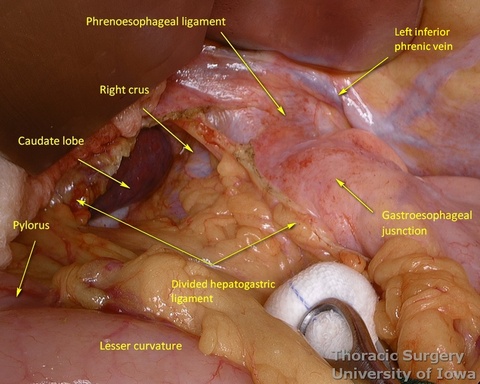

- The pars flaccida is incised and the gastrohepatic ligament is completely opened towards the esophageal hiatus.

- The right gastric artery is preserved

- The replaced/accessory left hepatic artery, if present, can be divided.

- Phrenoeosophagial ligament is formed by the transversalis fascia of abdomen and endothoracic fascia and is covered with the peritoneum. Thicker upper leaflet ascends obliquely and fuses with the adventitia of the esophagus above the diaphragm. The thinner lower leaflet runs caudally and attaches to the esophageal wall just cranial to the angle of His. The triangular space between the leaflets is filled with the perihiatal fat pad.

- The peritoneum is incised around the hiatus.

- The phrenoesophageal ligament is divided and the right crus dissected.

- Subhiatal fat ring is exposed after division of the lower leaflet of the phrenoesophageal ligament

- The abdominal esophagus, periesophageal fat, and nodes are dissected and encircled with a Penrose drain for retraction.